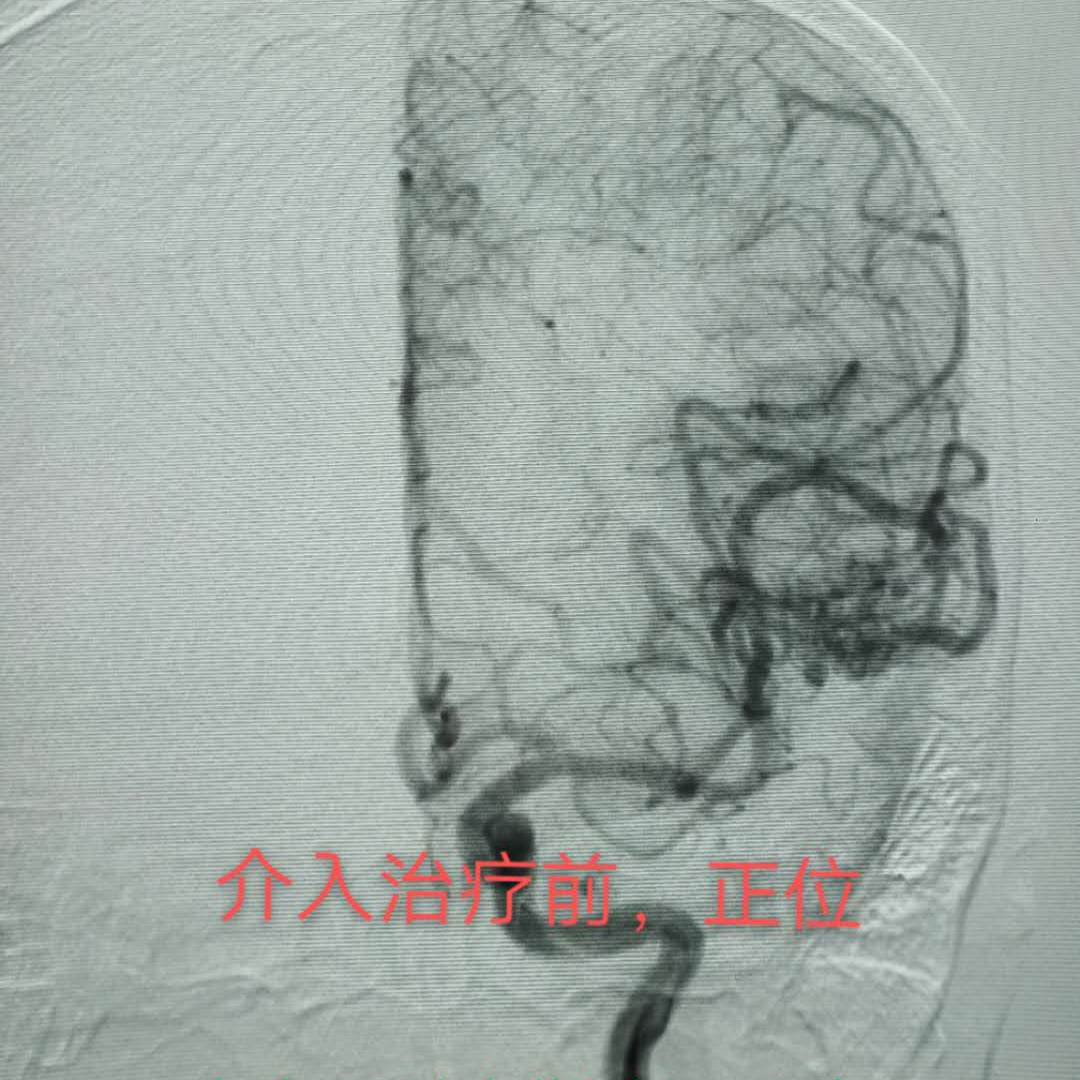

病例1 动脉入路

大多数情况下,通过介入治疗可以达到完全治愈的目的,针对部分患者血管内栓塞治疗是手术切除或放射外科治疗前的有效辅助治疗办法,通过一次或数次栓塞治疗将畸形团变小、栓塞其中的伴发动脉瘤、高流量动静脉瘘等,为手术、放射外科治疗创造条件。